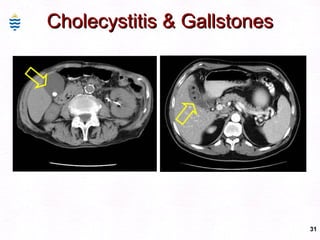

Cholecystitis & Gallstones Note thickened gallbladder wall. Inflammation. Mixed cholesterol & bile pigment stones.

Cholecystitis & Gallstones

Cholecystitis & GallstonesNote thickened gallbladder wall. Inflammation. Mixed cholesterol & bile pigment stones.